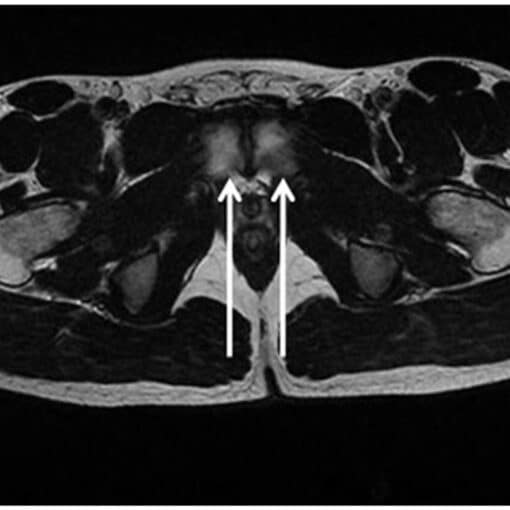

Η μαγνητική τομογραφία μπορεί να βοηθήσει σημαντικά στην κήλη των αθλητών, αλλά δεν αντικαθιστά την κλινική εξέταση. Δείχνει βλάβες σε προσαγωγούς, ηβική σύμφυση και ισχίο, αλλά έχει και όρια.